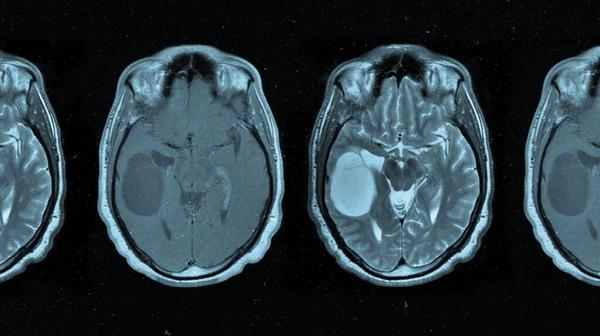

Choroid plexus tumor: Symptoms, treatment, and outlook

Choroid plexus tumors are growths in the area of the brain that produces cerebrospinal fluid (CSF). They may be cancerous or noncancerous. Choroid plexus tumors are rare. They develop in the choroid plexus, a network of cells lining the brain’s ventricles. Tumors in this area can disrupt the flow and production of CSF, leading to various neurological symptoms. Although these tumors can affect individuals of all ages, the benign type most commonly develops during childhood.

Oligodendroglioma: Symptoms, causes, and treatment

Oligodendroglioma is a rare type of slow-growing tumor of the central nervous system (CNS), which includes the brain and spinal cord. Treatment includes surgery, radiation therapy, and chemotherapy. Oligodendroglioma may arise in cells in the brain known as oligodendrocytes. These cells produce the protective sheath that surrounds nerves in the brain and spinal cord. Though uncommon, oligodendrogliomas can significantly affect a person’s neurological function and overall health.

Do pituitary tumors affect the optic nerves?

Pituitary tumors can compress the optic nerve, leading to visual symptoms. Pituitary tumors are mostly benign (noncancerous), but due to their location, they can have significant effects on surrounding structures within the brain and produce excess hormones. The optic nerve is responsible for vision. It is above the pituitary gland, and a pituitary tumor can place pressure on the nerve, leading to visual disturbances or loss of vision.

Parasagittal meningiomas: Symptoms, and how to treat them

Parasagittal meningiomas are tumors located in the middle space of the brain, between the two hemispheres. They can also grow into a nearby vein called the superior sagittal sinus. Most parasagittal meningiomas tend to be slow-growing and noncancerous. Still, treatment is necessary as they can cause pressure on the brain, which may cause serious health problems, such as seizures or problems with coordination. This article explores parasagittal meningiomas, their symptoms, and treatment.

Medulloblastoma: Subtypes, symptoms, treatment, and more

Medulloblastoma is a brain tumor predominantly affecting children. It is aggressive and challenging to treat, but outcomes are often optimistic. Medulloblastoma is a central nervous system tumor. It originates in the cerebellum, which is at the lower back part of the brain. The cerebellum is crucial for motor control. The challenge with medulloblastoma lies in its aggressive growth and potential to metastasize, or spread, to the spinal cord.